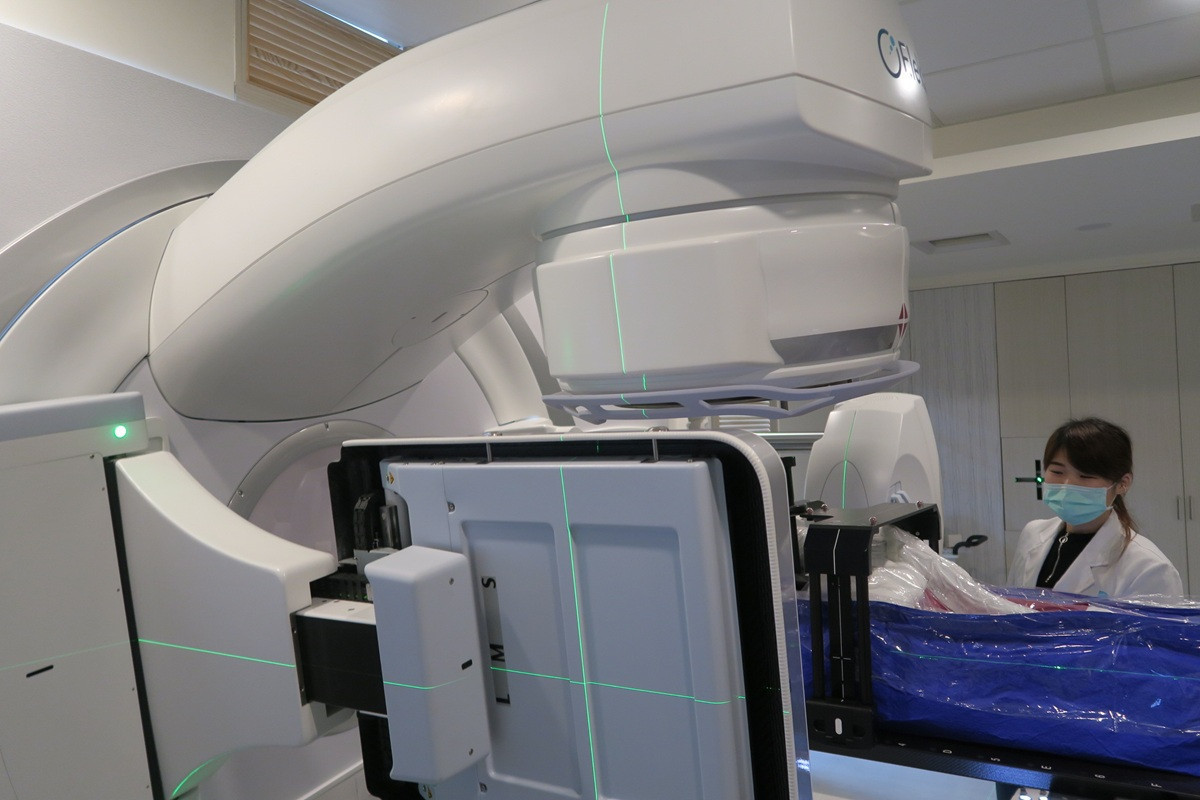

面對如此兩難情境,張博竣指出,林先生身體狀況虛弱,若採用化學治療,恐難以承受其副作用,風險極高。經過多次與林太太深入溝通,反覆討論治療目標、生活品質與現實條件,醫療團隊最終與家屬達成共識,採單純放射線治療,在兼顧安全的前提下,為病人保留希望。

林先生隨即展開為期兩個月、共35次俗稱「電療」的放射線治療。療程結束後,原本巨大、外觀明顯的腫瘤幾乎完全消失,治療反應遠超預期。這個結果,不僅讓醫療團隊振奮,也為家屬帶來久違的笑容。

張博竣表示,林先生身體狀況差、治療選項有限,同時面臨家屬意見分歧、家庭支持力不足與經濟考量等多重壓力。在這樣的條件下,選擇全健保給付的放射線治療,幾乎沒有額外花費,卻仍獲得顯著成效,更凸顯「量身打造治療策略」的重要性。